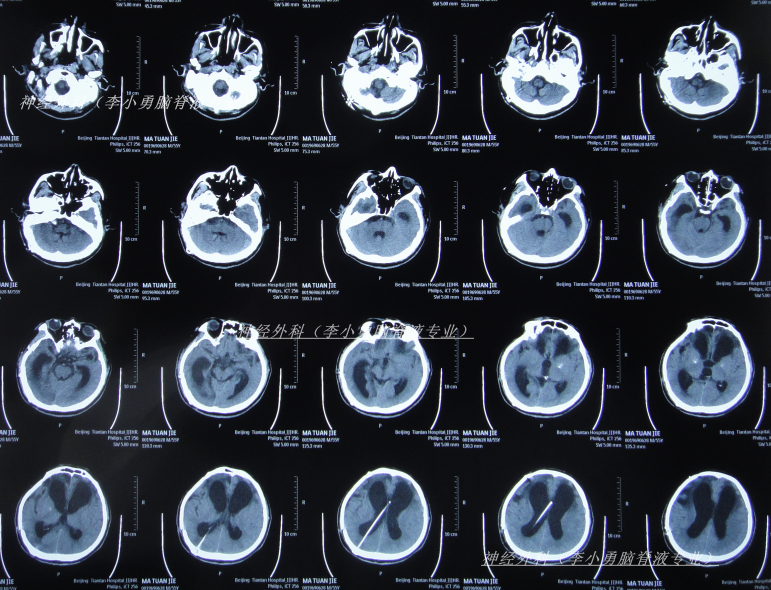

因症状没有改善,决定到北京就诊,经过考虑在李小勇脑脊液专业和北京某三甲医院,选择了北京某三甲医院,2025年1月10日(颅骨修补术后85天即脑室腹腔分流术后113天),住入北京某三甲医院,查头颅CT(图-6)和腰穿检查后考虑颅内感染,给予抗感染治疗。

图-6:2025年1月10日头颅CT

治疗4天后即2025年1月13日,仍发热,查头颅CT(图-7)和肺部CT(图-8)后继续抗感染治疗。

图-7:2025年1月13日头颅CT

保守治疗1周没有效果,于2025年1月18日(颅骨修补术后93天即脑室腹腔分流术后121天),再次选择了北京另一所三甲医院,查头颅CT(图-9)后急诊留观,行脑脊液检查提示人类疱疹病毒。

图-9:2025年1月18日头颅CT

该院治疗10天即2025年1月27日,查头颅CT示脑室进一步扩张(图-10)。

图-10:2025年1月27日头颅CT